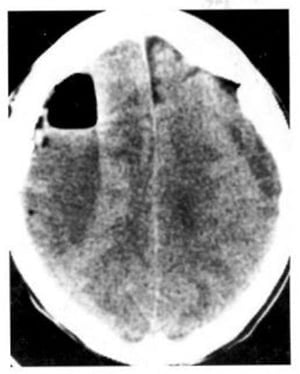

Hình 1.43. Khối máu tụ tươi trong não ở một trẻ nhỏ. Máu có mật độ cao trong bán cầu não bên phải, phù mật độ thấp bao quanh. Tụ dịch mãn dưới màng cứng hai bên. Đây là một trường hợp trẻ bị bạc đãi.